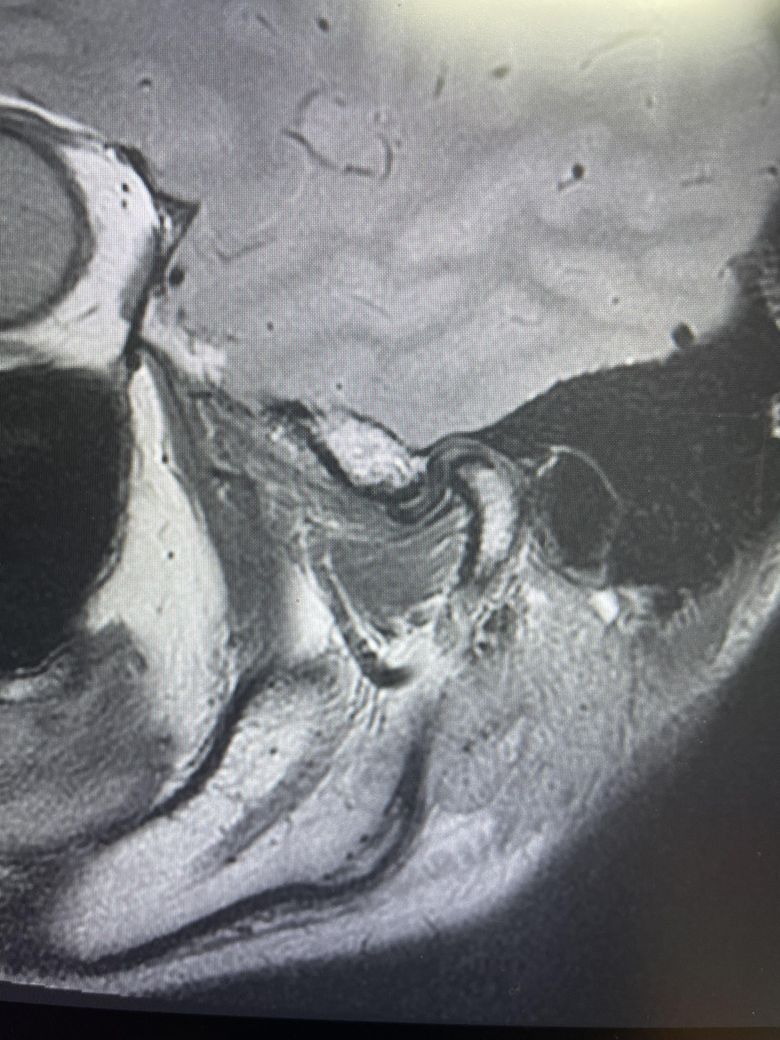

구강내과 턱 MRI 어느 사진이 우측? 좌측?인지 어떻게 보나요? 디스크 두꺼워짐 심한가요?ㅜ

구강내과 턱 MRI 사진 보는데 귀 위치가 다 똑같아서요

어느 사진이 우측? 좌측?인지 어떻게 보나요?

그리고 사진 상 디스크 두꺼워짐 심한가요?ㅜ

현재 사진만으로는 정확히 왼쪽이나 오른쪽이다 라고 할 수 없습니다. 이는 데이터 상의 reference가 필요하며 보통은 해당 부위가 질문자님 기준으로 좌측일 가능성이 가장 크나 이는 좌우 반전을 할 수 있기 때문에 무조건 좌측이라고 할 수 없습니다. 현재 개구시와 폐구시에 보았을 때 condyle (아래턱 부위의 일부)가 disc를 넘어가지 못하고 있으며 이러한 경우 개구제한이 있거나 넘어가더라도 소리가 나면서 넘어갈 수 있습니다. 일부 염증도 보이고 있으므로 내과적인 치료를 하셔야 할 것으로 보입니다.